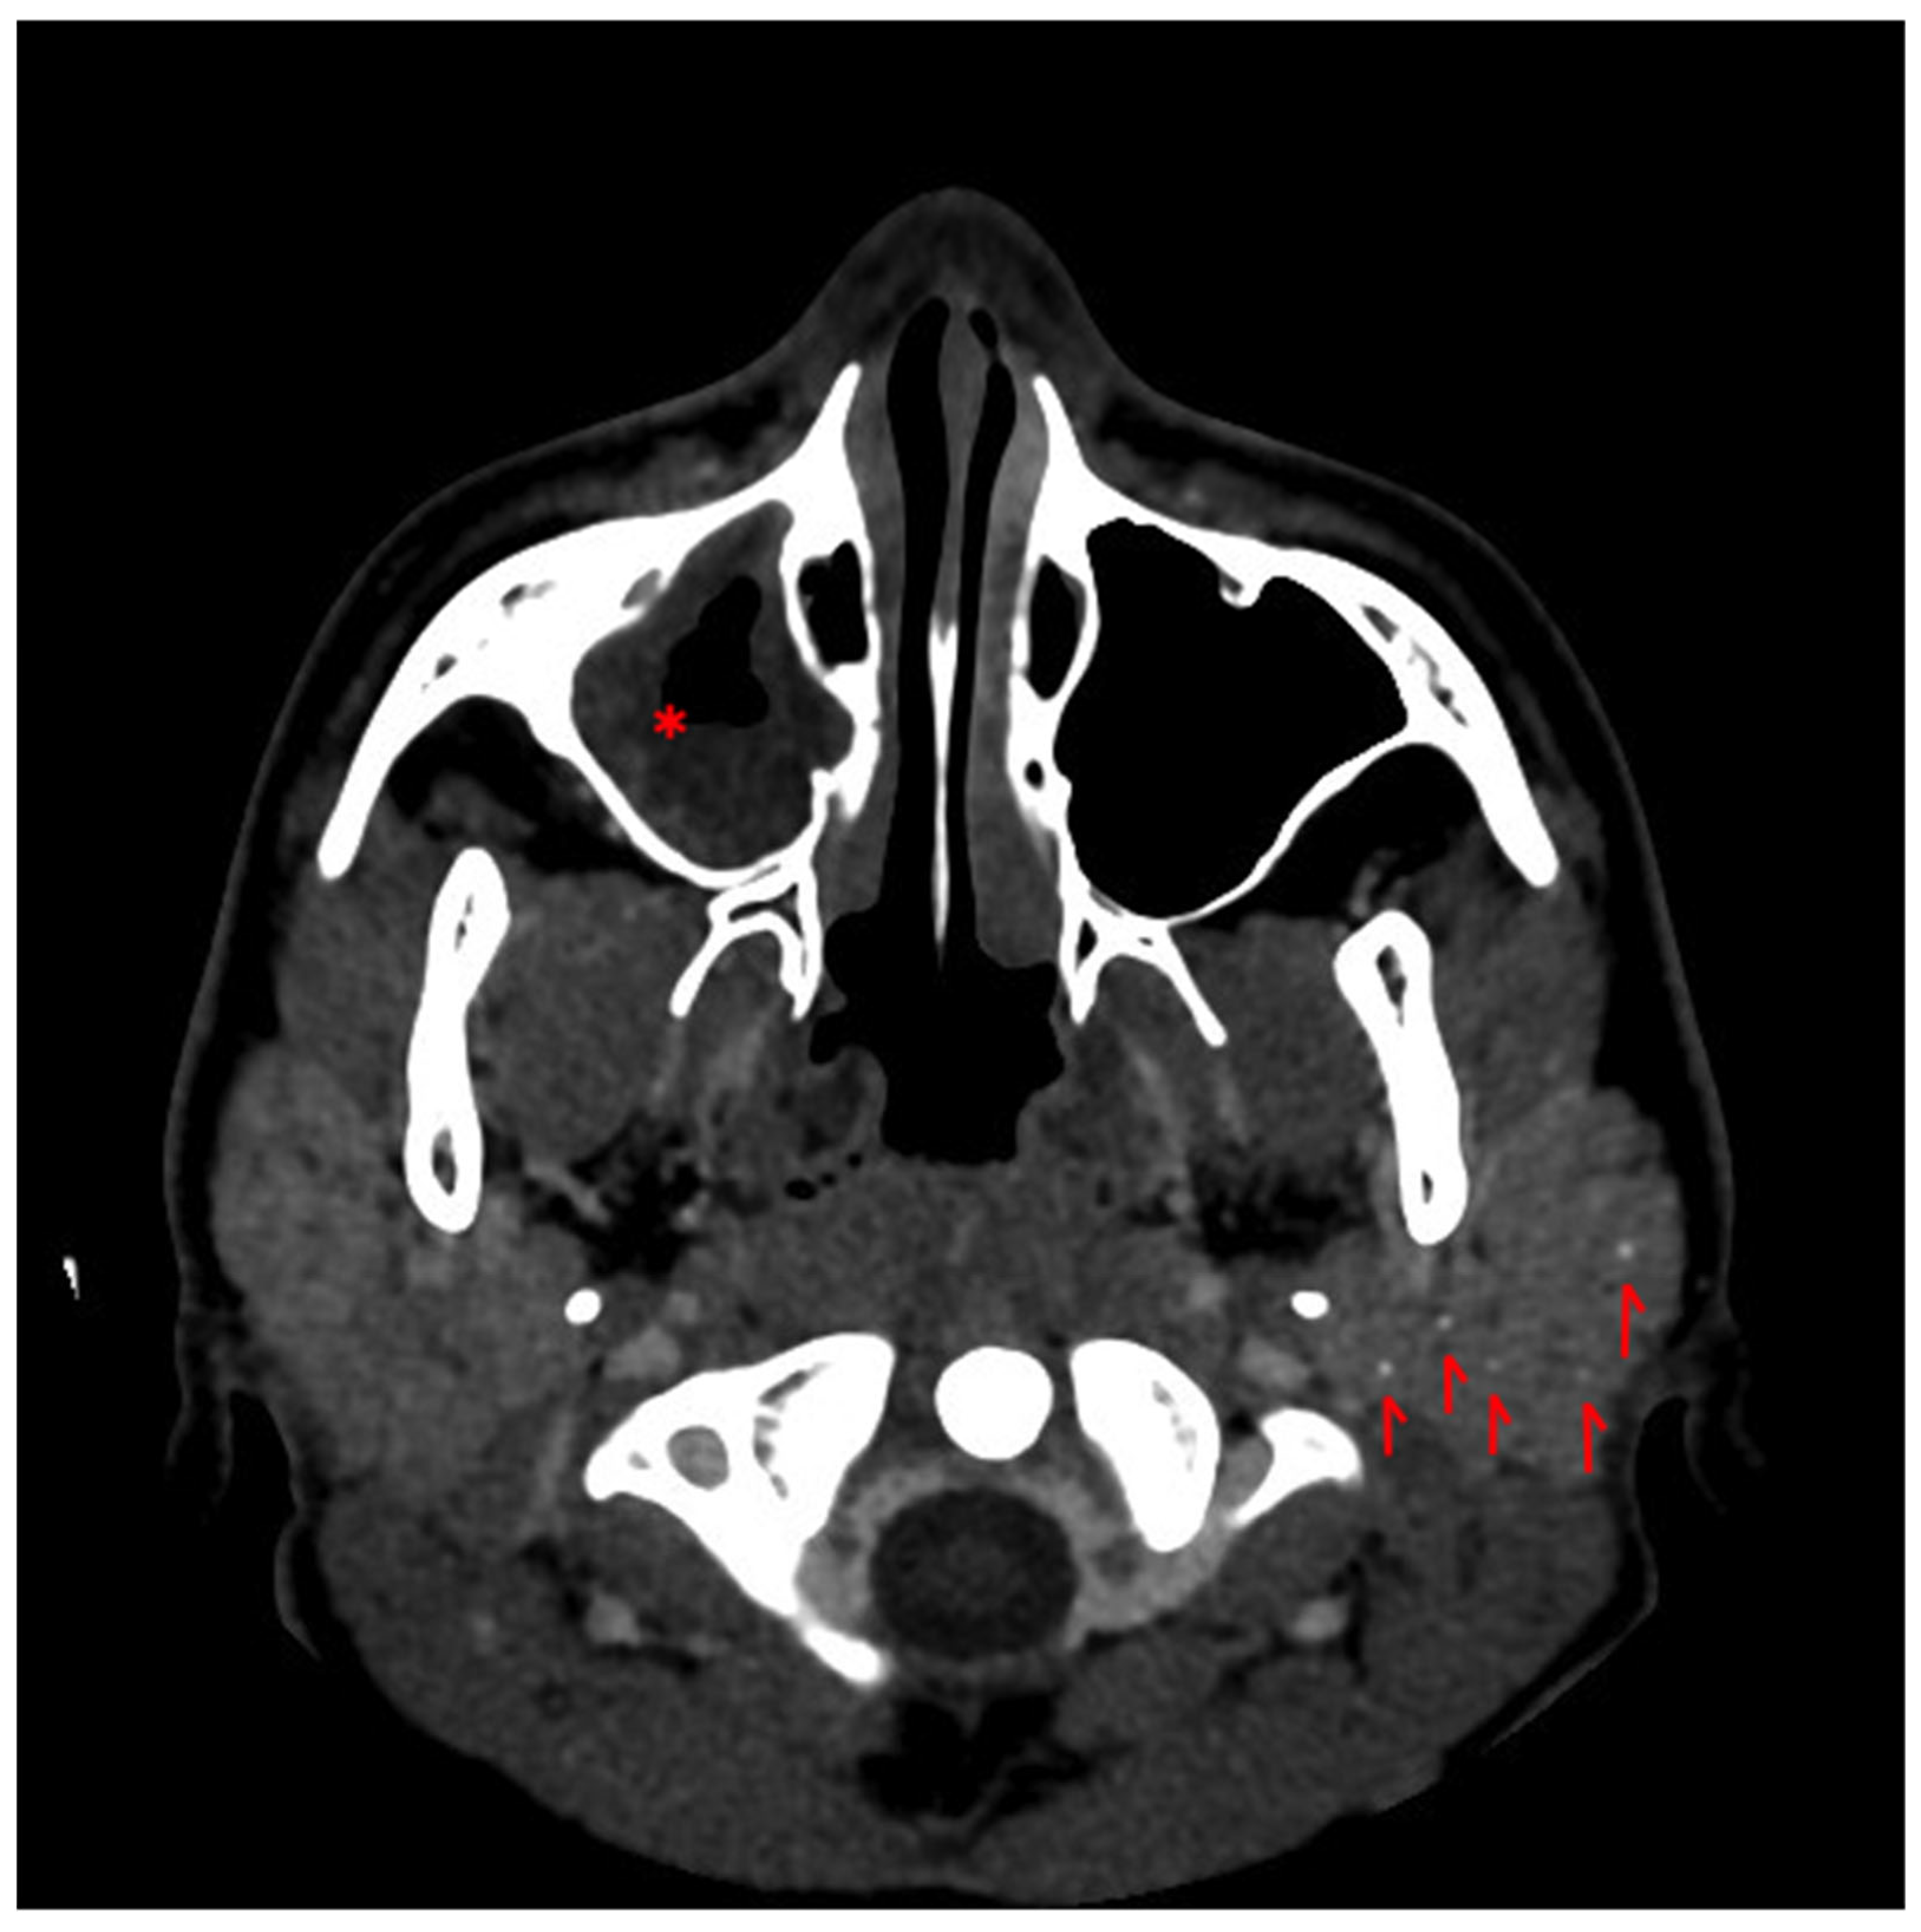

2. Case Report